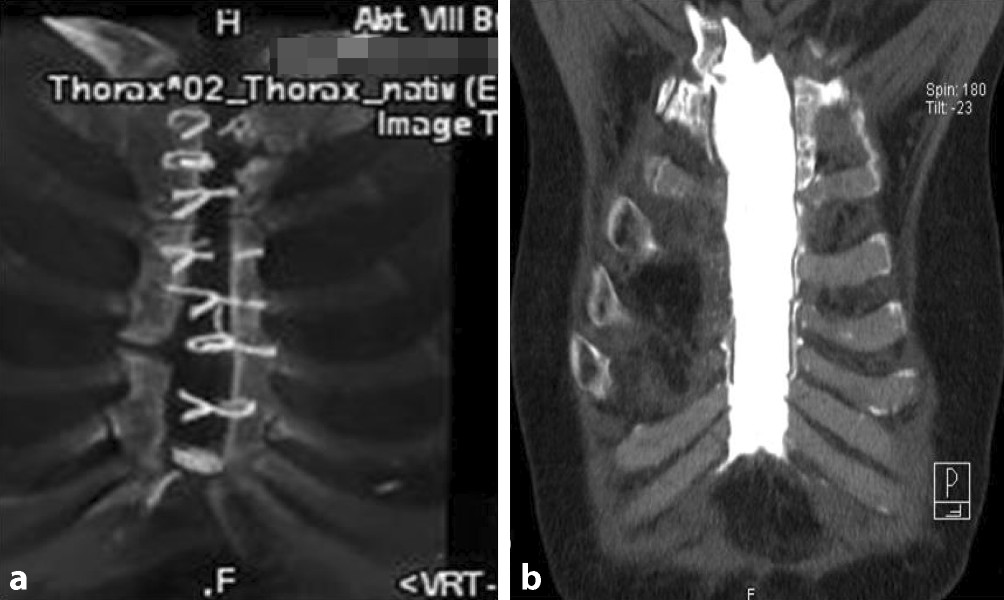

Zur Sicherung der Diagnose und Operationsplanung wurde regelhaft eine Computertomographie des Thorax angefertigt, um die knöcherne Situation am Brustbein individuell zu beurteilen (Abb. 1).

Abb. 1

Präoperative Computertomographie zur Beurteilung der zu erwartenden Defektgröße und zur Planung der operativen Versorgung. a Volume-Rendering-Technik (VRT) – Darstellung aus dem CT-Datensatz. b Fisteldarstellung im CT bei sonst geschlossener Narbe über dem Sternum mit Kontrastmitteldarstellung